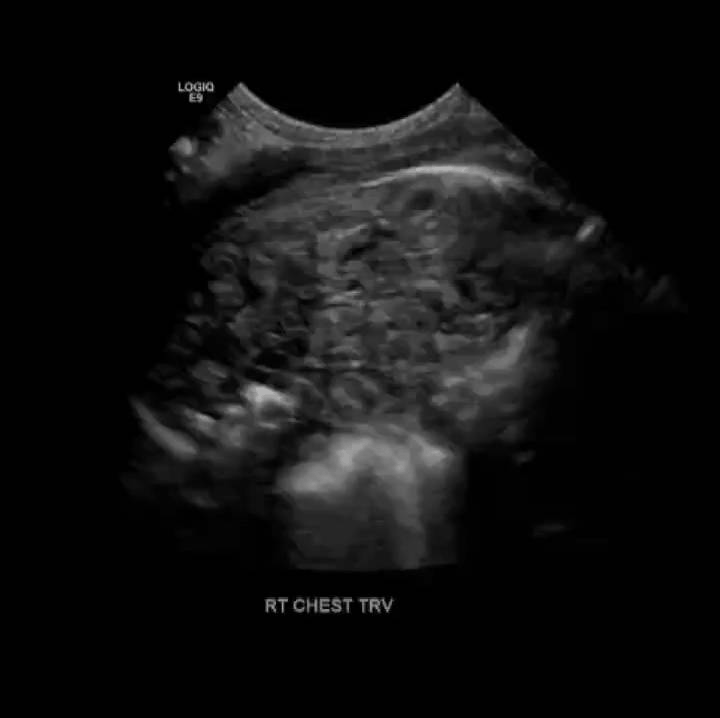

Diaphragmatic Hernia

Congenital diaphragmatic hernia is a defect or hole in the diaphragm that allows abdominal contents to enter the chest cavity. Most cases are diagnosed prenatally. Neonates typically present with respiratory distress acutely after birth. The lung on the affected side is usually hypoplastic.

Diapharagmatic hernias are usually classified by location.